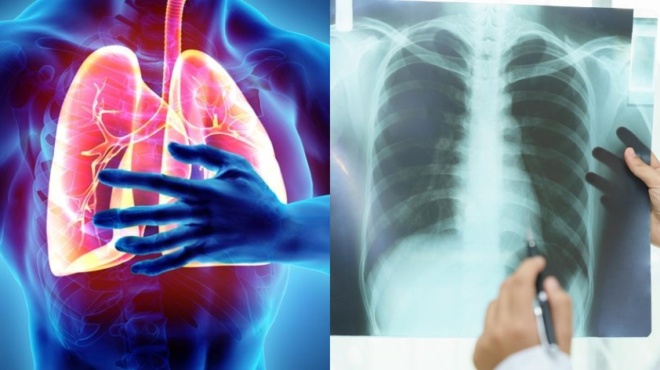

Οι γιατροί του Royal Preston Hospital στο Λάνκασιρ της βορειοδυτικής Αγγλίας πίστευαν πως ο ασθενείς τους έχει καρκίνο στον πνεύμονα. Τον έστειλαν βιαστικά για να κάνει τις απαραίτητες εξετάσεις. Η έκπληξη τους ομως ηταν τεράστια όταν είδαν πως αντί για καποιον όγκο ο ασθενείς είχε σφηνωμένο στον πνεύμονα του ένα μικρο playmobil.

Ο 47χρονος είχε καταπιεί το παιχνίδι όταν ήταν παιδί. Το αξιοπερίεργο ηταν πως δεν είχε παρουσιάσει κανένα σύμπτωμα. Τουλάχιστον οχι επί τέσσερις δεκαετίες. Τα πρώτα συμπτώματα που παρουσίασε ηταν έντονος βήχας με φλέμα και έπειτα έντονη αδιαθεσία. Συνήθως εάν ο οργανισμός μας αντιληφθεί καποιο ξένο σώμα τότε προσπαθεί να το αποβάλει.

Ειδικοί λένε ότι ουδέποτε στο παρελθόν ένα αντικείμενο δεν είχε παραμείνει επί τόσο διάστημα κρυμμένο στον οργανισμό ενός ασθενούς. Το παιχνίδι αφαιρέθηκε τελικά στο χειρουργείο.

Πρόκειται για μια ασυνήθιστη στα ιατρικά χρονικά περίπτωση για ενήλικες, που περιγράφεται ως «ξένο σώμα τραχειοβρογχικού δέντρου». Ωστόσο είναι συνηθισμένη σε παιδιά. Τέσσερις μήνες μετά την επέμβαση ο βήχας του εξαφανίστηκε κι έχει σχεδόν αναρρώσει πλήρως.